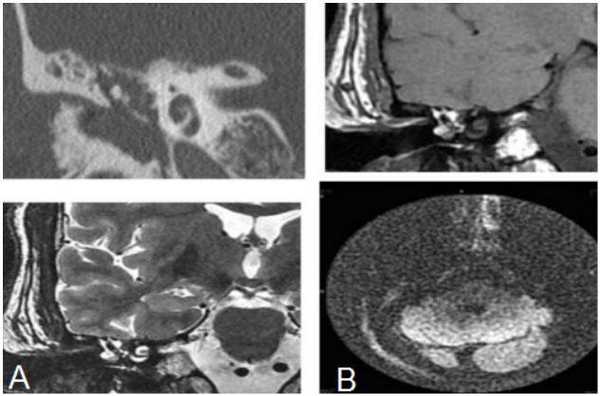

Пациентке была выполнена МРТ основания черепа по описанной методике (рис. 1). Рисунок 1. МРТ основания черепа больной Ф. с хроническим правосторонним гнойным средним отитом. Фистула лабиринта. Холестеатома. а — исследование в режиме Т1; б — в режиме Т2; в — в режиме non-EPI DWI.

В режиме Т1 справа определяется образование с низкой интенсивностью сигнала, а в режиме Т2 и non-EPI DWI — образование с гиперинтенсивным сигналом. Диагноз: хронический правосторонний гнойный средний отит; холестеатома; фистула лабиринта. Пациентка была подвергнута санирующей операции на правом ухе с тимпанопластикой и облитерацией паратимпанальных пространств. Были выявлены холестеатома, заполняющая аттик, адитус, антрум, деструкция цепи слуховых косточек, фистула латерального полукружного канала. Послеоперационный период протекал без особенностей, на 15-е сутки была удалена гемостатическая губка и силиконовая выстилка. При контрольном осмотре ухо сухое, отмечает улучшение слуха, головокружения нет. Через 12 мес проведено повторное МРТ-исследование. Признаков холестеатомы не обнаружено. Получен хороший функциональный результат — ухо толерантно к воде, самоочищается.

На КТ височных костей справа послеоперационная полость, заполненная мягкотканным образованием, определяется большой костный дефект в направлении сигмовидного синуса и мозжечка (рис. 2, а). Рисунок 2. КТ и МРТ височных костей больной У. с хроническим правосторонним средним отитом. Состояние после радикальной операции (1993 г.), санирующей операции с мастоидопластикой и тимпанопластикой (2003 г.). Холестеатома. Парез лицевого нерва. а — КТ; б — МРТ основания черепа в режиме Т1; в — в режиме Т2; г — в режиме non-EPI DWI.

Больной была выполнена МРТ (рис. 2, б—г).

В режимах Т2 и non-EPI DWI определяется сигнал высокой интенсивности, в режиме Т1 — низкоинтенсивный сигнал. Это может свидетельствовать о наличии холестеатомы мастоидальной полости и пирамиды височной кости. Диагноз: хронический правосторонний средний отит; состояние после радикальной операции в 1993 г. и санирующей операции с мастоидопластикой и тимпанопластикой в 2003 г.; холестеатома; парез лицевого нерва.

На КТ правой височной кости определяется затемнение в области аттика и антрума, цепь слуховых косточек сохранена (рис. 3, а). Рисунок 3. КТ и МРТ височных костей больного А. с адгезивным средним отитом справа, фиброзной облитерацией аттика. а — КТ; б — МРТ основания черепа в режиме Т1; в — в режиме Т2; г — в режиме non-EPI DWI.

Пациенту выполнена МРТ основания черепа по описанной методике (рис. 3, б—г).

В режиме Т1 и Т2 справа определяется очаг с высокой интенсивностью сигнала, тогда как в режиме non-EPI DWI патологических образований не выявлено. Диагноз: адгезивный средний отит справа, фиброзная облитерация аттика.